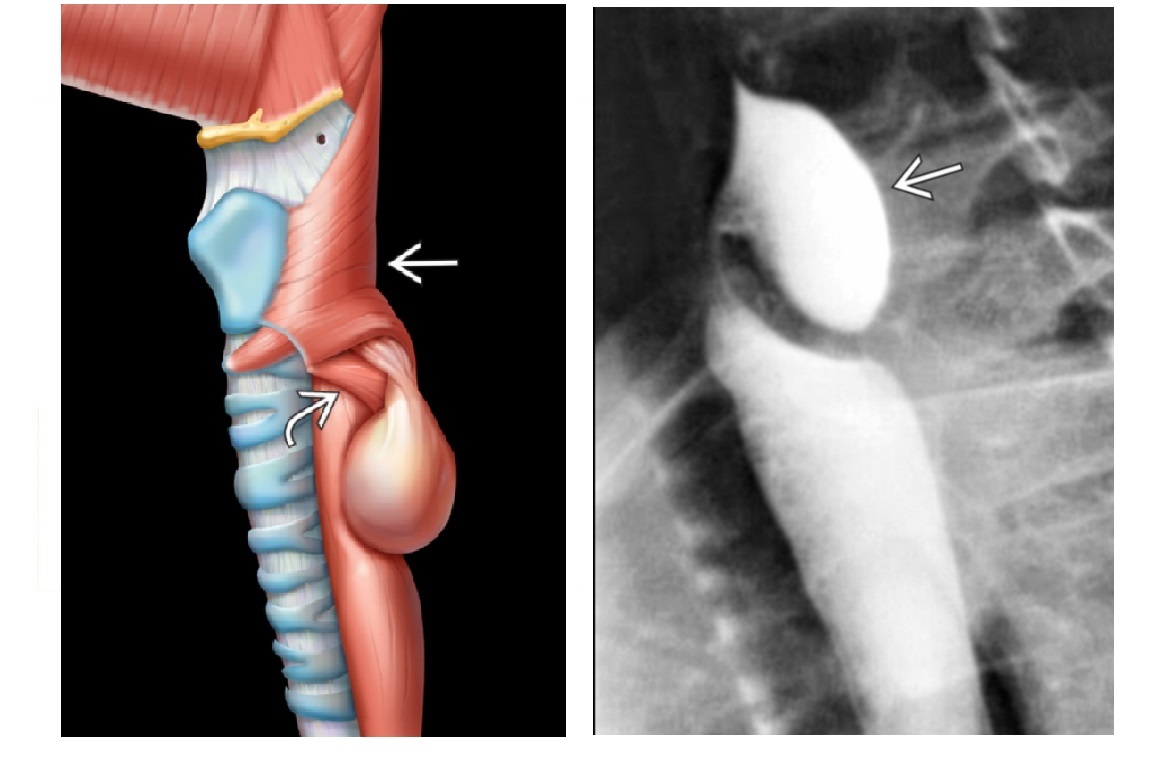

Zenker Diverticulum

Outpouching with rounded contour posteriorly in the neck is above the cricopharyngeus muscle

In hypopharynx!!!

Site of weakness is the Killian dehiscence - between the inferior pharyngeal constrictor muscle and cricopharyngeal muscle

Epiphrenic diverticulum

Large saccular outpouching just above the diaphragm, right side

Can be mistaken for paraesophageal hernia - usually in on the left

associated with dysmotility disorders